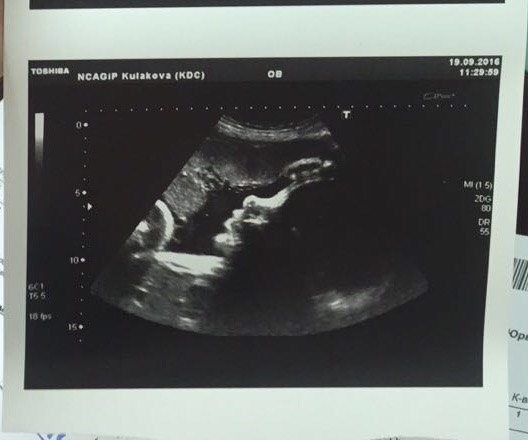

Итак ) контракт в Кулакова заключён 👍 "роды в радость" до октября ещё есть , но по поводу цен не консультируют , при мне отправляли приходить за информацией позже , у кого срок нескоро .. узи прошло быстро , но чётко) лежим головкой вниз , без обвития , все в норме ) Огай поставила 2600 малышу ) ой, люблю не могу 😍😍была на приёме у Кесовой , до чего же приятнейший человек и врач!👍👍я в восторге! День у неё был сумасшедший , ждала час с лишним , не смотря на то , что по записи , но это стоило того...